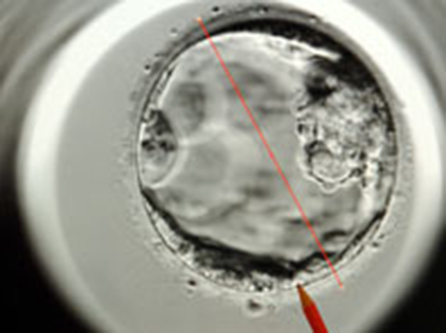

Университет Оксфорда придумал, как повысить шансы на рождение ребенка посредством ЭКО. Как передает BBC, нужно просто проверять ток энергии в эмбрионе. Ученые проанализировали активность митохондрий ("энергетических фабрик" клеток) 111 эмбрионов. Оказалось, если активность митохондриальная была аномальной, то показатель имплантации равнялся 0%.

В принципе, сейчас, согласно принятому стандарту, эмбрионы проверяют на правильный набор хромосом, генетическую информацию, которая увеличит шансы на успех ЭКО. По факту, даже если набор нормален, возможны проблемы. Британские ученые рекомендуют включать в медицинскую практику проверку митохондрий (оценку уровня митохондриальной ДНК в пятидневных эмбрионах).

Выяснилось: 76% подсаженных эмбрионов, которые выглядели физически нормальными, имели нормальные хромосомы и нормальную митохондриальную активность. Но 0% эмбрионов имплантировались, если были аномалии в митохондриях, даже когда выглядели они нормально. К счастью, подобные проблемы выявляются лишь у 10% эмбрионов. По словам ученых, причина, видимо, кроется в какой-то стрессовой реакции.